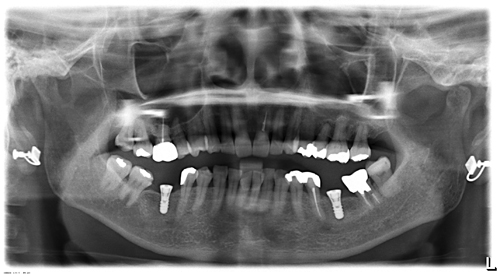

術前のレントゲン写真です

歯周病や虫歯など細菌感染による疾病は原則的に術前に治していますので、悪い歯を取った後のように腫れることは少ないです。